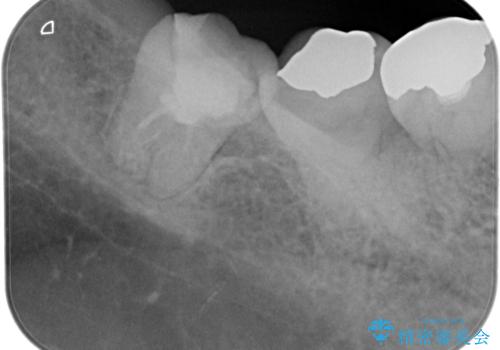

【根管治療】噛んだ時にしみる。最近になってズキズキ痛み、長引く痛みがある

- 噛んだ時にしみる。最近になってズキズキ痛み、長引く痛みがある。とのことで来院されました。

検査結果にて不可逆性歯髄炎の診断を行いました。

顕微鏡にて虫歯を取り除くと、深いクラックラインを認めることができ、クラックラインを全て除去し抜髄処置を行いました。